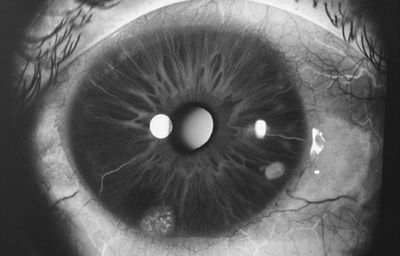

Clínicamente se manifiesta como un tumor circunscrito o difuso.

El circunscrito, es una masa solitaria nodular en el estroma del Iris, con variables grados de pigmentación, con vasos nutricios intrínsecos en el estroma o dentro del ángulo. (31,32,33)

Melanoma sólido nodular del Iris

Archivo Fotográfico Dr. Francisco Barraquer.